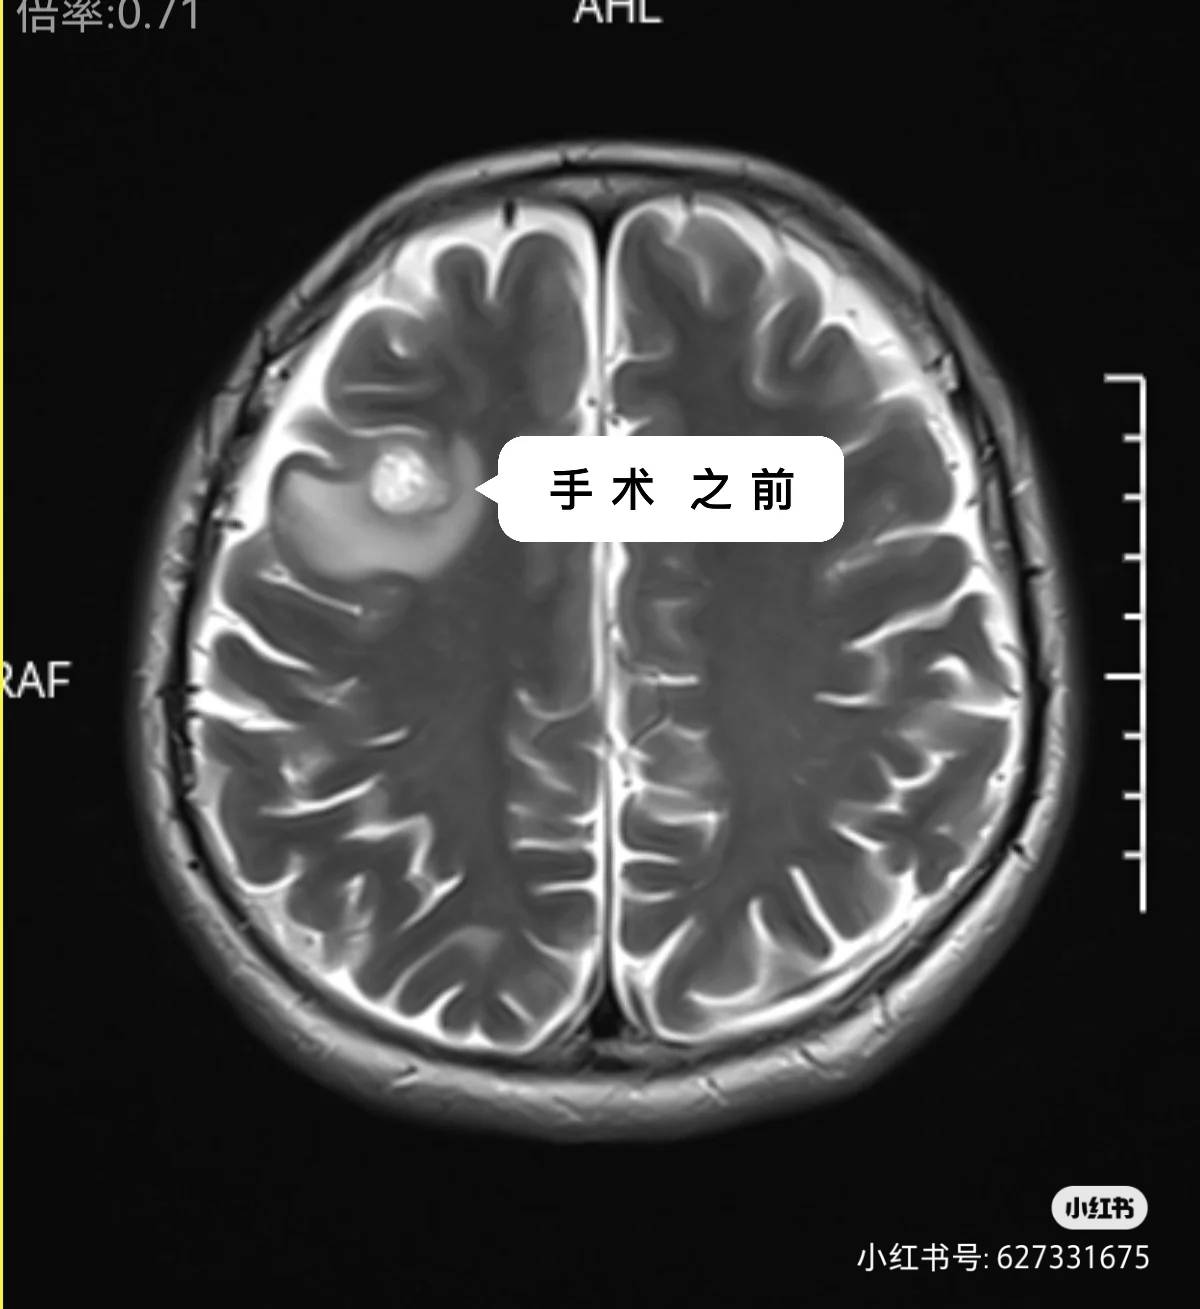

先发现的脑转移,吃了一个多月的奥西替尼,复查不见小,做了伽马刀。